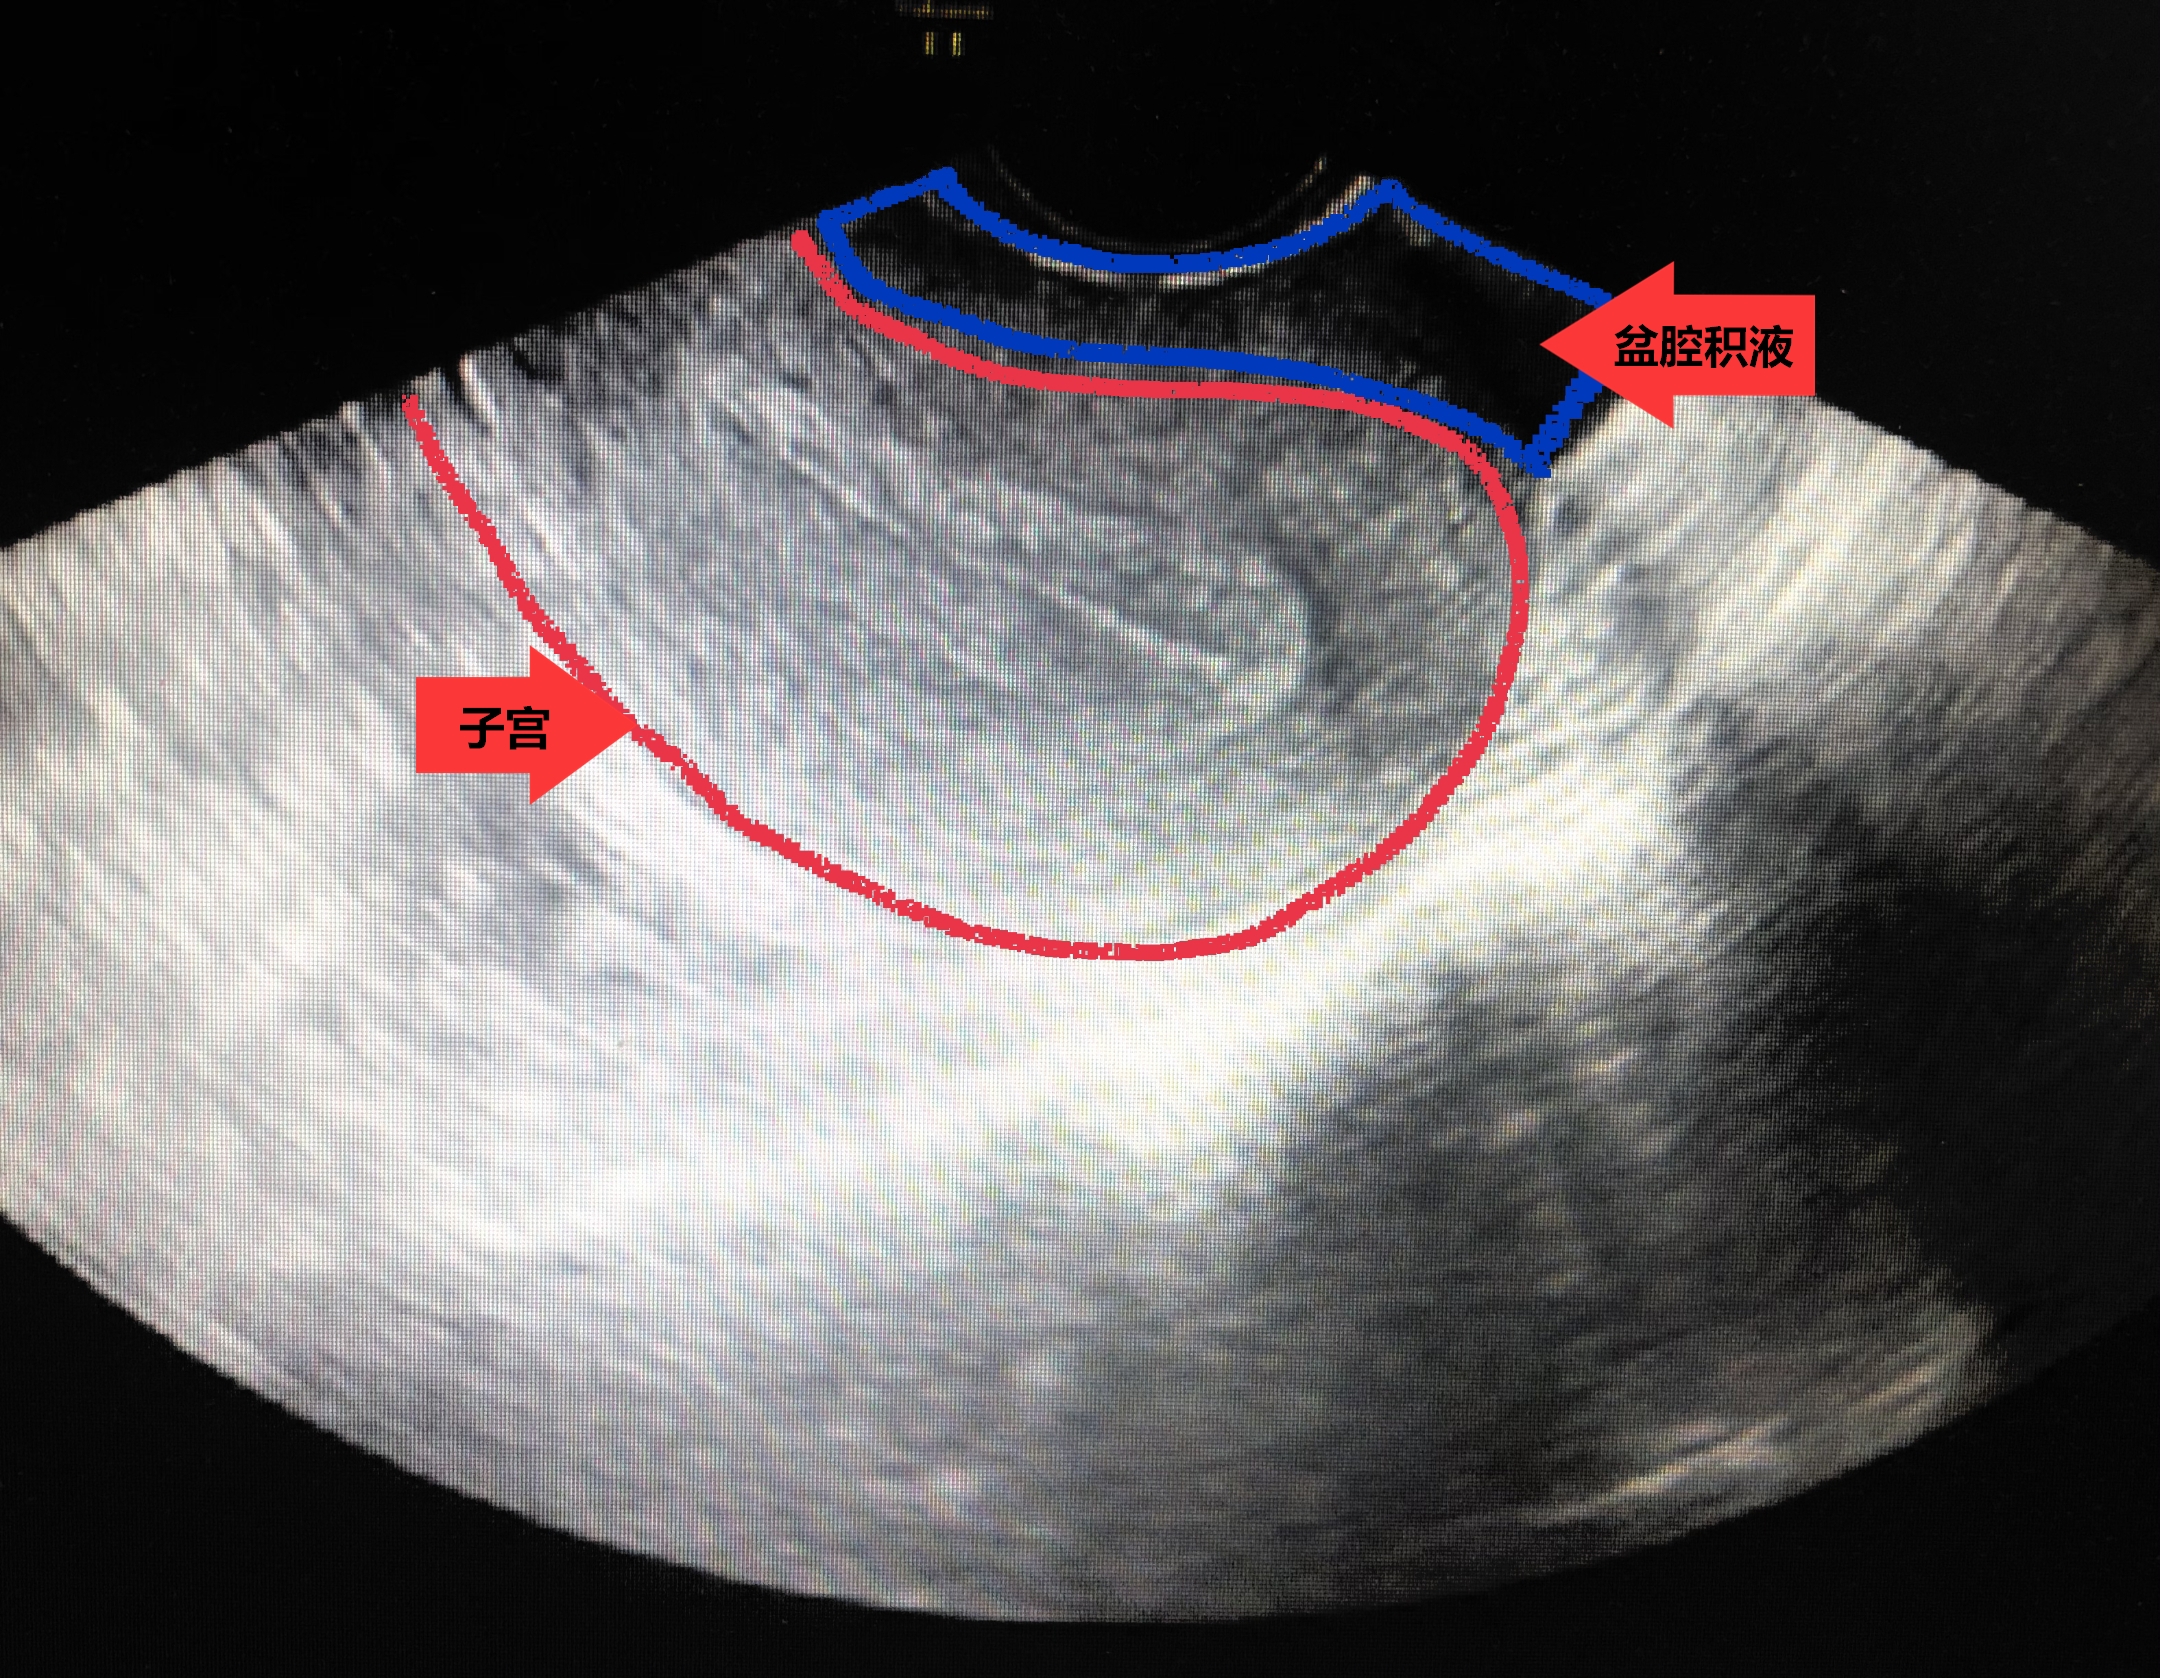

盆腔积液按发生的原因分为生理性盆腔积液(见图一)和病理性盆腔积液(见图二)。生理性盆腔积液——因为盆腔是腹腔在全身最低的部位,当有渗出液或漏出液时都会流至盆腔,从而形成盆腔积液。部分正常女性在月经期或排卵期会有少量血液聚集在盆腔从而形成盆腔积液。这类女性往往没有任何临床症状,不需要特殊治疗积液可以自行消失。因此当碰到少量盆腔积液时,我们完全不必过分紧张,只需要继续观察。

图一 生理性盆腔积液,特点:量少,透声好